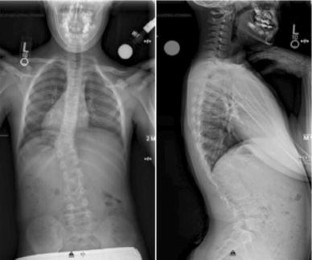

Fig. 2